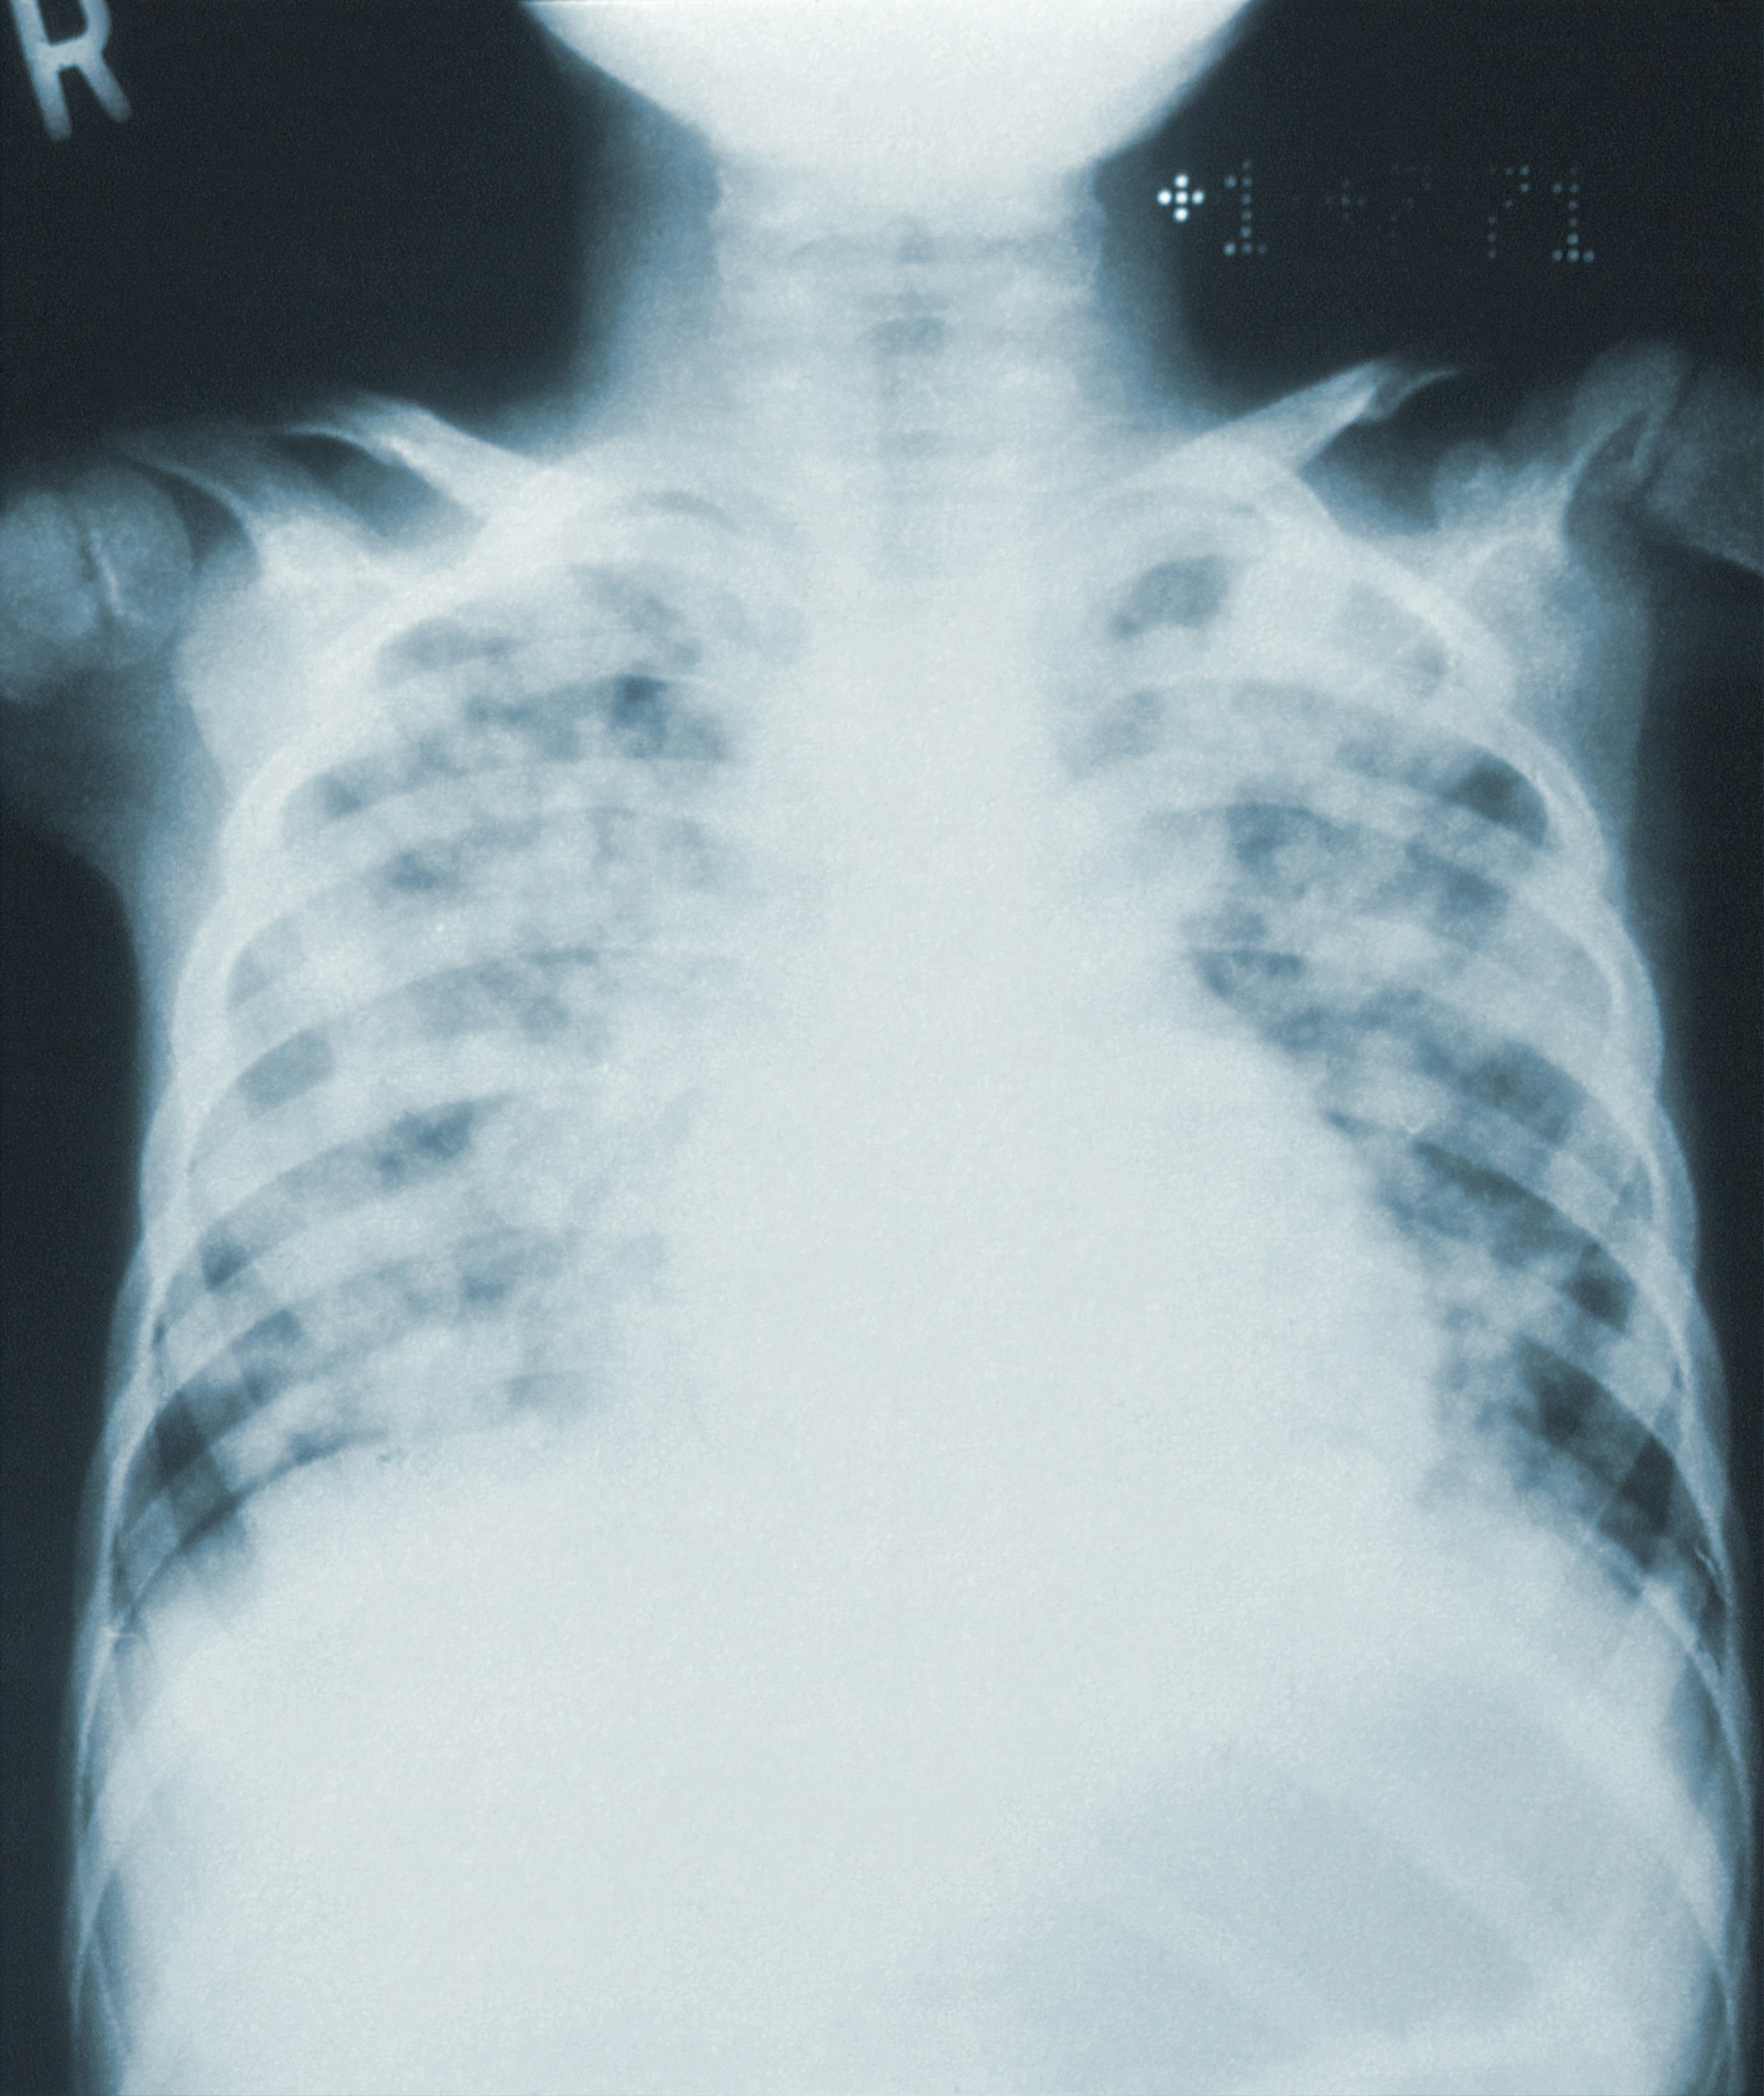

So I contacted my oncology team through the portal, and my oncologist said to go to my primary care doc and get covid and flu testing along with an EKG and chest X-ray.

I was pleasantly surprised that my PCP office had an EKG machine, so I managed to knock out the covid and flu testing and EKG in one place. Both covid and flu were negative, and the EKG looked fine. But the PA did hear some fluid in my lungs and gave me an order to get a chest x-ray.

And luckily again the imaging center wasn't far away, and I squeaked in as the next-to-last patient they took for the day. So I got the chest x-ray completed.

Next I got a message from the PA through that portal, and that was the x-ray results. I typically don't look at results because I don't know the medical terminology and often think things are worse than they actually are. I did read this one, and sure enough it worried me.

I sent those x-ray results to my oncologist.